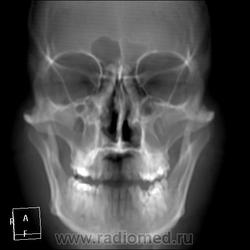

КТ ППН и носоглотки. Девушка 21 года. Полипозный риносинусит.

Госпитализирована для оперативного лечения. Удалены полипы носа. Вторым этапом планируется гайморотомия. Во время операции - подозрение на образование носоглотки. Сохраняется затруднение носового дыхания. Направлена на КТ. Категорически отказалась от контрастировния (лекарственная полиаллергия, боится).

Полип в носоглотке справа. Нарушена пневматизация придаточных пазух носа кроме левой решётчатой. В левой гайморовой на дне неясно что…

На дне гайморовой - полип, в носоглотке немаленький хоанальный полип. Там всё в полипах, а они и фиброзные бывают, и ангиофибромы, и ангиоаденомы... Вот и плотность разная.